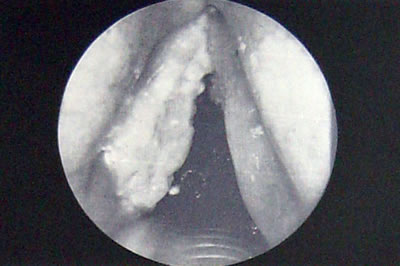

◆喉頭がん

・喉頭がんは50〜70歳の男性に好発します。(男女比10:1)

・患者さんの97%以上が愛煙家(ヘビースモーカー)です。

・症状:かすれ声、のどの異物感、嚥下痛(飲み込み時痛)、呼吸困難、等

・かすれ声が1ヶ月以上の長期にわたり頑固につづく人は要注意です。耳鼻咽喉科を受診してみましょう。